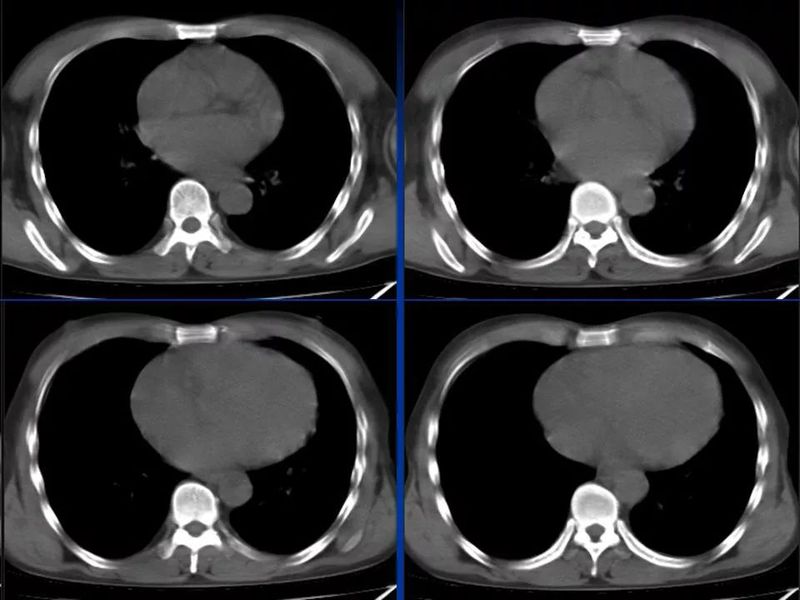

主任提醒:这个病很容易误诊为肺炎!